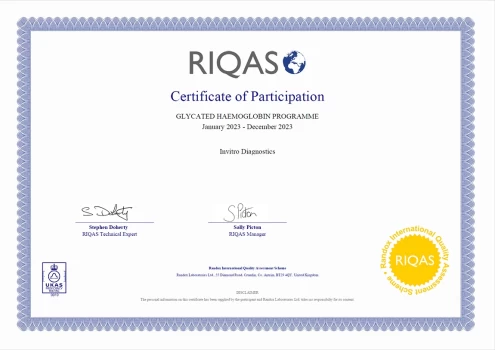

Certificate